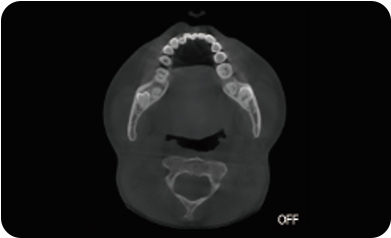

临床样片